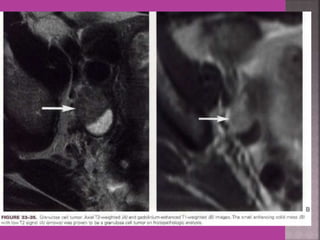

 Myoma—to differentiate myoma from

adenomyoma.localization of myoma—sub

serous/ intra mural or sub mucous.

Degeneration Of Fibroid

Cystic Degeneration of

Fibroid

 Study ofnormal uterus and adnexa – with aim to have clear image of normal myometrium, endometrium , ovary and follicles within the ovary.  Myoma—to differentiate myoma from adenomyoma.localization of myoma—sub serous/ intra mural or sub mucous.  Adenomyosis---accurate diagnosis.  Congenital uterovaginal anomalies— bicornuate, septate,subseptate , unicornuate, didelphys ,rudimentary horn and vaginal atrasia etc